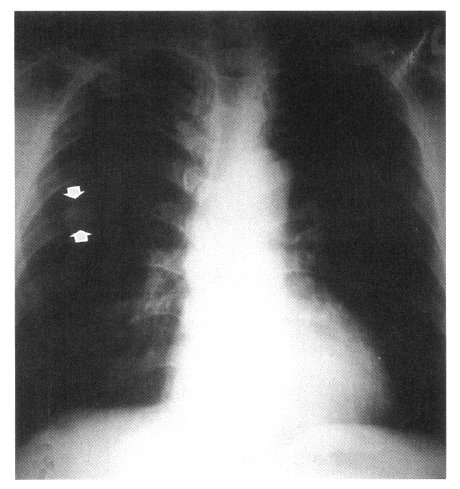

Figure 1.

Initial chest radiograph shows a solitary pulmonary nodule in the right upper lung (arrow).